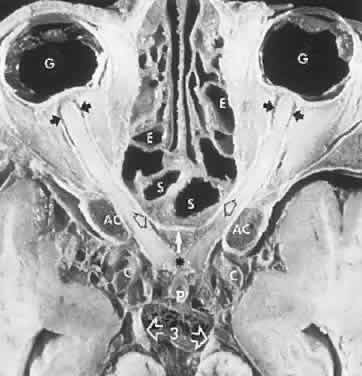

METABOLIC STORAGE DISORDERS

Biochemical assays have considerably clarified the nosologic status of the group of storage diseases previously classified as the “cerebromacular degenerations,” of which Tay-Sachs disease is the eponymous prototype. Although these disorders share a superficial resemblance, showing a progressive neurodegenerative course with variable fundus findings, they are now best classified by abnormal storage products (e.g., sphingolipidoses, mucopolysaccharidoses, and mucolipidoses) and lysosomal enzyme deficiencies. Lysosomes contain hydrolytic enzymes that degrade proteins, polysaccharides, and nucleic acids; if undegraded, these materials accumulate in lysosomes and impair cell function. The complex lipids and saccharides indigenous to neural cells produce symptoms and signs related to eye and brain, including corneal clouding, macular “cherry-red spot,” pigment epithelial degenerations, optic atrophy, mental deterioration, seizures, motor incoordination, myoclonus, and death.

The ganglion cell layer of the retina is a principal site of abnormal accumulation of anomalous storage products, such that ophthalmoscopic changes are observable either in the form of retinal “graying” or the well-known cherry-red spot. The ganglion cell layer densely surrounds the thin fovea, which transmits the normal red color of underlying choroid (Fig. 4). The storage disorders with cherry-red spot or macular graying are listed in Table 2.27

Fig. 4. “Cherry-red spot” of advanced Tay-Sachs disease (gangliosidosis). Note the central foveal window surrounded by a ring of densely opaque retinal ganglion cell layer; also, optic atrophy.